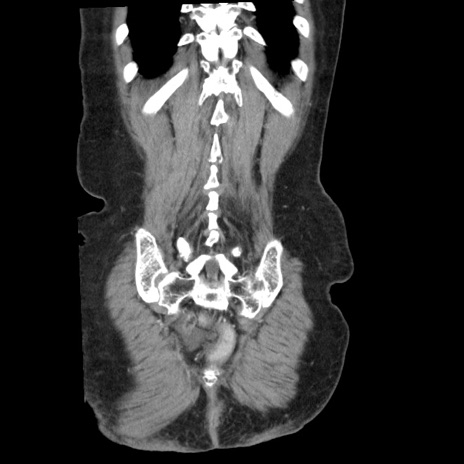

矢状断像

【症例】80歳代女性

【主訴】腹痛

【現病歴】8時間前から腹痛あり来院。

【既往歴】糖尿病、脂質異常症、子宮体癌にて子宮全摘術

【身体所見】意識清明・会話良好だが腹痛で苦悶様、全腹部にわたって反跳痛と圧痛あり

【データ】WBC 13600、CRP 0.14、LDH 224、CK 90